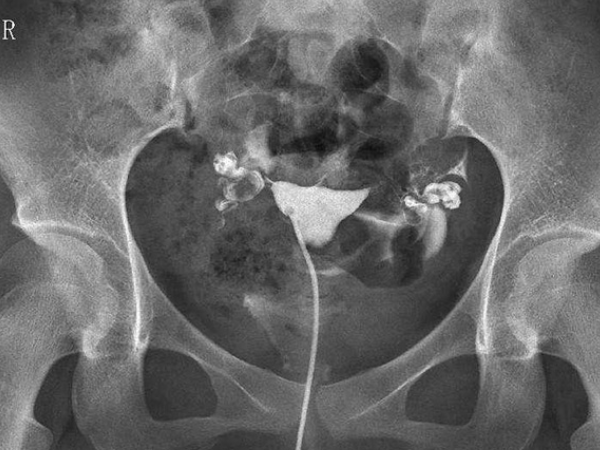

小手指自測輸卵管通暢的辦法並沒有科學道理,大多數都是個人的經驗之談,想要正確地檢測輸卵管是否通暢應該到醫院做檢查才能得知,檢查手段包括子宮輸卵管造影、輸卵管通液與腹腔鏡檢查等